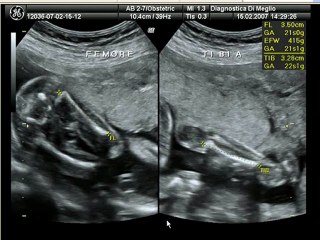

Ecografia Ostetrica 20 settimane

User: Aniello Di Meglio